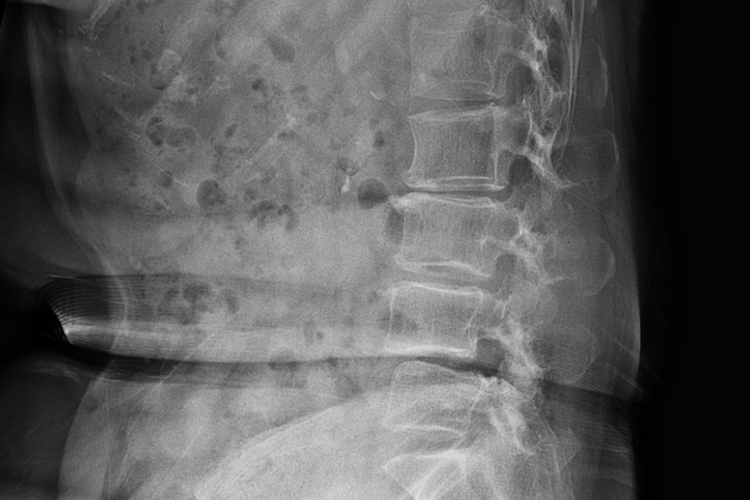

脊柱外观

腰椎间盘突出患者脊柱大多表现为腰椎生理前凸变浅,严重的患者生理前凸可完全消失,甚至出现腰后凸。部分的患者可以出现腰椎的侧凸,如果突出物在神经根的内侧,则凸向健侧。相反,如果突出物在神经根的外侧,则凸向患侧。在腰椎间盘突出时,腹部各方向活动度都会不同程度地受影响,其中以前屈受限最明显。

根据病史、症状、体征以及在X线平片上相应的节段有椎间盘退行性改变者,即可做出初步诊断,结合X线、CT、MRI等方法,能准确做出病变间隙、突出方向、突出物大小、神经受压情况的诊断。